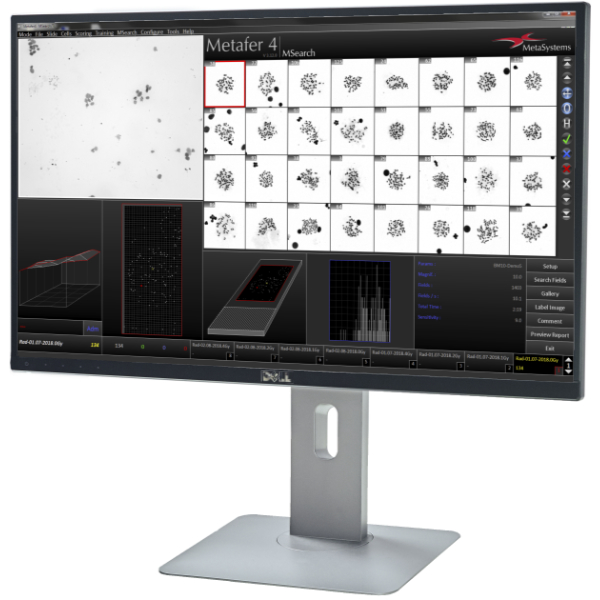

Metafer is a software platform designed to manage standard microscopes and related hardware. It facilitates the scanning of light microscope slides, the acquisition of digital images, the application of standard image processing techniques, and the measurement of general image features.

- Review all imaging results in a well-organized image gallery.

- Efficiently relocate identified objects on the microscope with a single mouse click.

Utilizing the Metafer software, imaging systems scan specimens of diverse sizes, employ various contrasting methods and magnifications, and identify, classify, and enumerate cells or other objects. Metafer's modularity and flexible architecture make it proficient in assisting users from various fields with their specific imaging tasks.

In contrast to complex analysis systems that can be unwieldy and challenging to navigate, Metafer's intelligent scanning offers a different experience: unhindered access to all data, a user-friendly display of results, and complete control over imaging parameters to ensure precise results according to your preferences. With Metafer, slide scanning becomes remarkably straightforward.